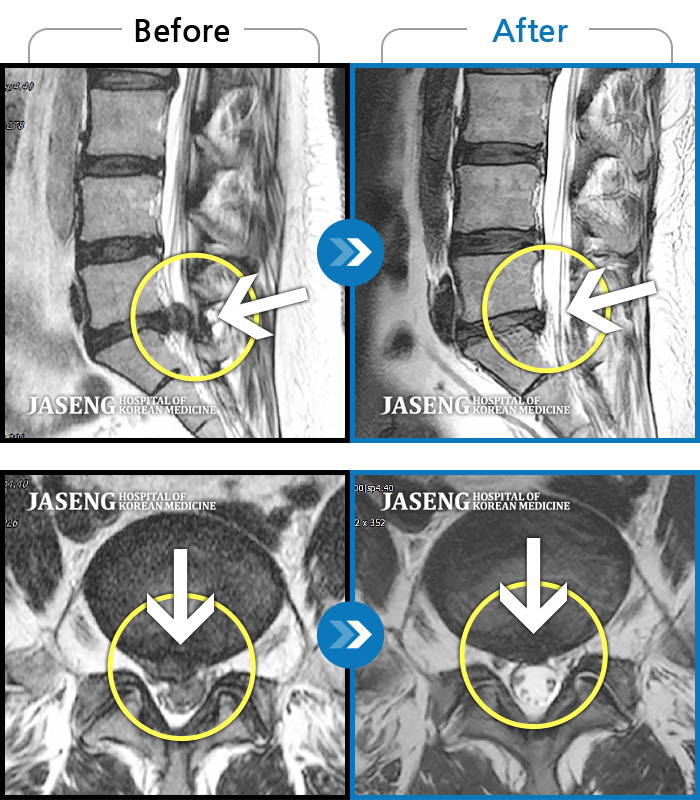

허리디스크

강남 · 강만호 원장

허리 통증 및 왼쪽 다리 근력저하 감각저하로 일상생활이 불가능했습니다.

촬영시기

2024.05.18 ~ 2025.12.03

2025.12.19